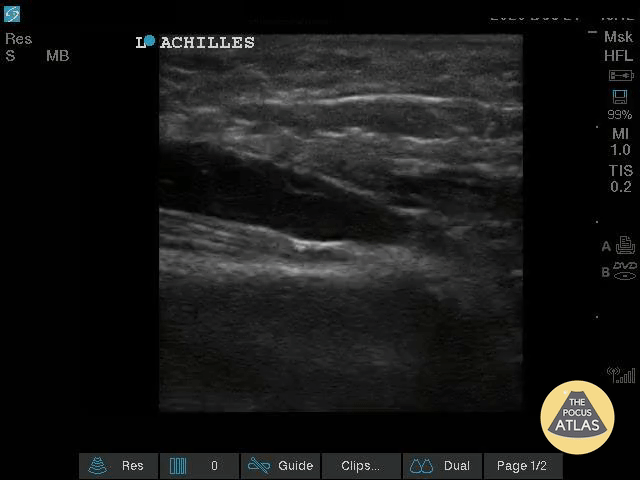

Musculoskeletal - Nearly Complete Achilles Tear

Healthy male in late-20s trying to do a backflip off a diving board. Still was able to plantarflex (very weak and with significant pain). Submitted by Dr. Elias Jaffa